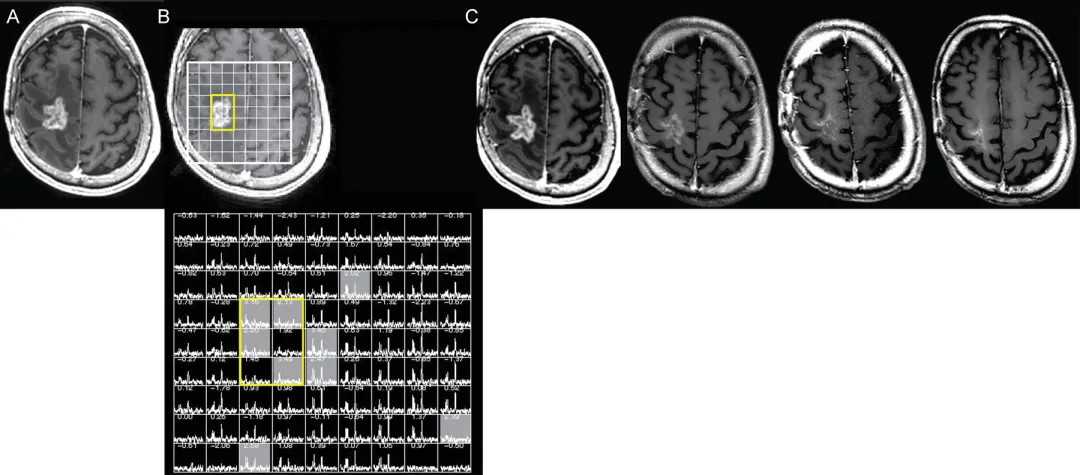

磁共振波谱成像

磁共振波谱成像(MRS)作为体素内代谢物标记的无创手段,也可辅助诊断真性进展(图4)。脑血容量与磁共振波谱方法的汇总分析显示,与假性进展相比,真性进展组的胆碱/N-乙酰天冬氨酸比值与胆碱/肌酸比值显着升高。确定合适截断值存在挑战,有研究报道采用对侧脑组织胆碱/胆碱比值的敏感度低至33%,而其他研究报道敏感度与特异度均超过90%。此外,在强化区域内,对侧脑组织肌醇/肌酸比值降低与乳酸/谷氨酰胺+谷氨酰胺比值升高均与真性进展相关。磁共振波谱的局限性还在于其对异常区域体素定位的依赖,根据磁共振场强差异,获得足够信噪比所需的体素尺寸为1-8立方厘米,限制了该技术检测微小病灶变化的能力。尽管磁共振波谱单独诊断效能因技术限制存在差异,但联合扩散/灌注加权成像可提高整体准确性已达成共识。

图4.磁共振波谱辅助判定假性进展。右侧额叶胶质母细胞瘤放疗后12个月疑似复发—A:轴位T1加权增强MRI显示结节状环形强化占位伴坏死。B:病变三维质子磁共振波谱显示N-乙酰天冬氨酸与胆碱显着降低(黄色轮廓),提示治疗相关改变而非肿瘤复发。C:连续8个月的四幅轴位T1加权增强MRI显示强化病灶进行性缩小,治疗未改变。